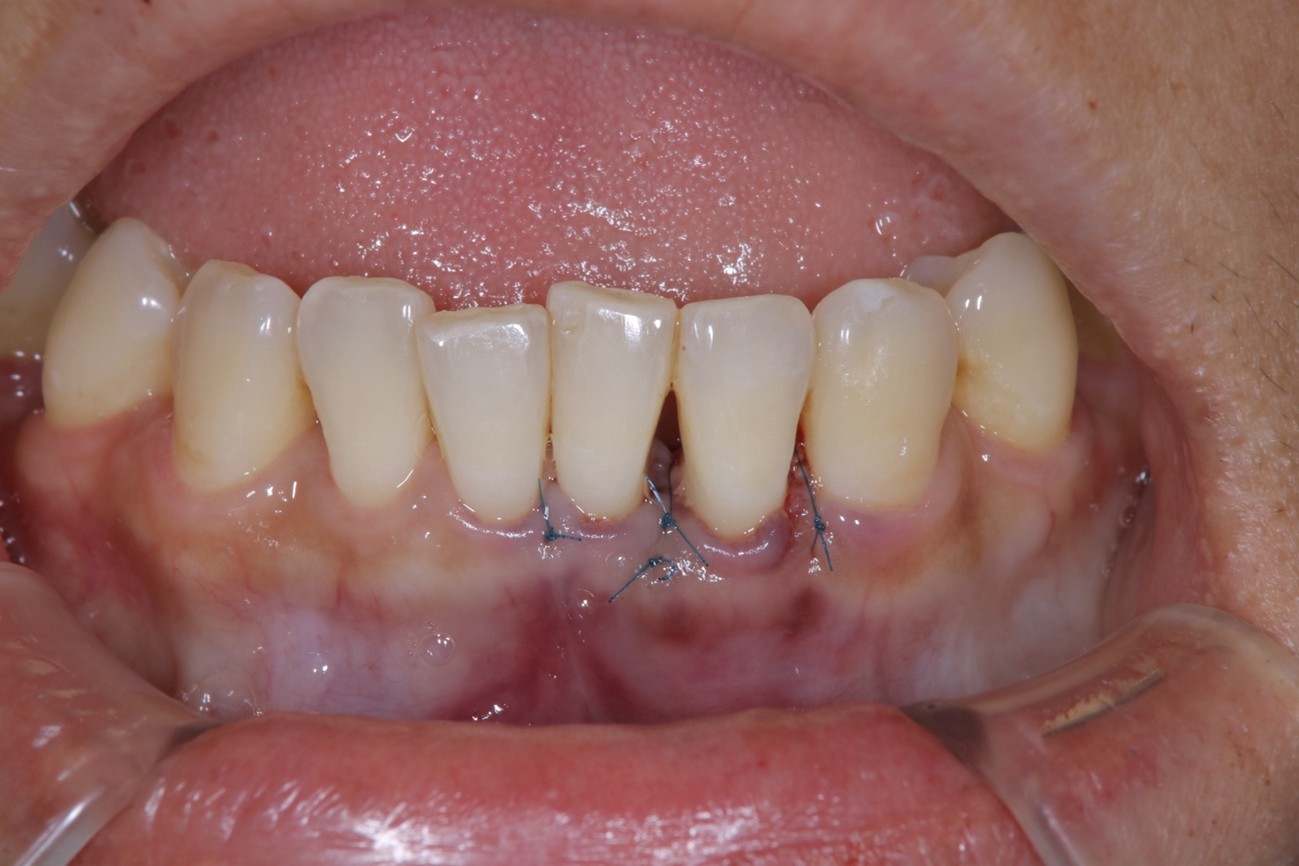

治療方法:患部の清掃・再生のお薬(エムドゲイン)・自家骨の移植により骨の再生を促します。

治療結果:歯茎からの出血や膿が止まり、さらに骨の再生が確認できた。